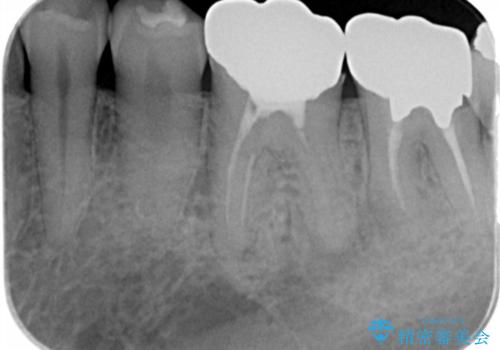

- 銀歯・虫歯・治療途中の歯を治していきたい、セラミックの歯にしたい!と希望され来院されました。

銀歯の下で再発した虫歯や、根尖病変等、多々の問題が認められましたがひとつづつ丁寧に改善し、長期的な予後の見込めるセラミック治療を行っていきます。